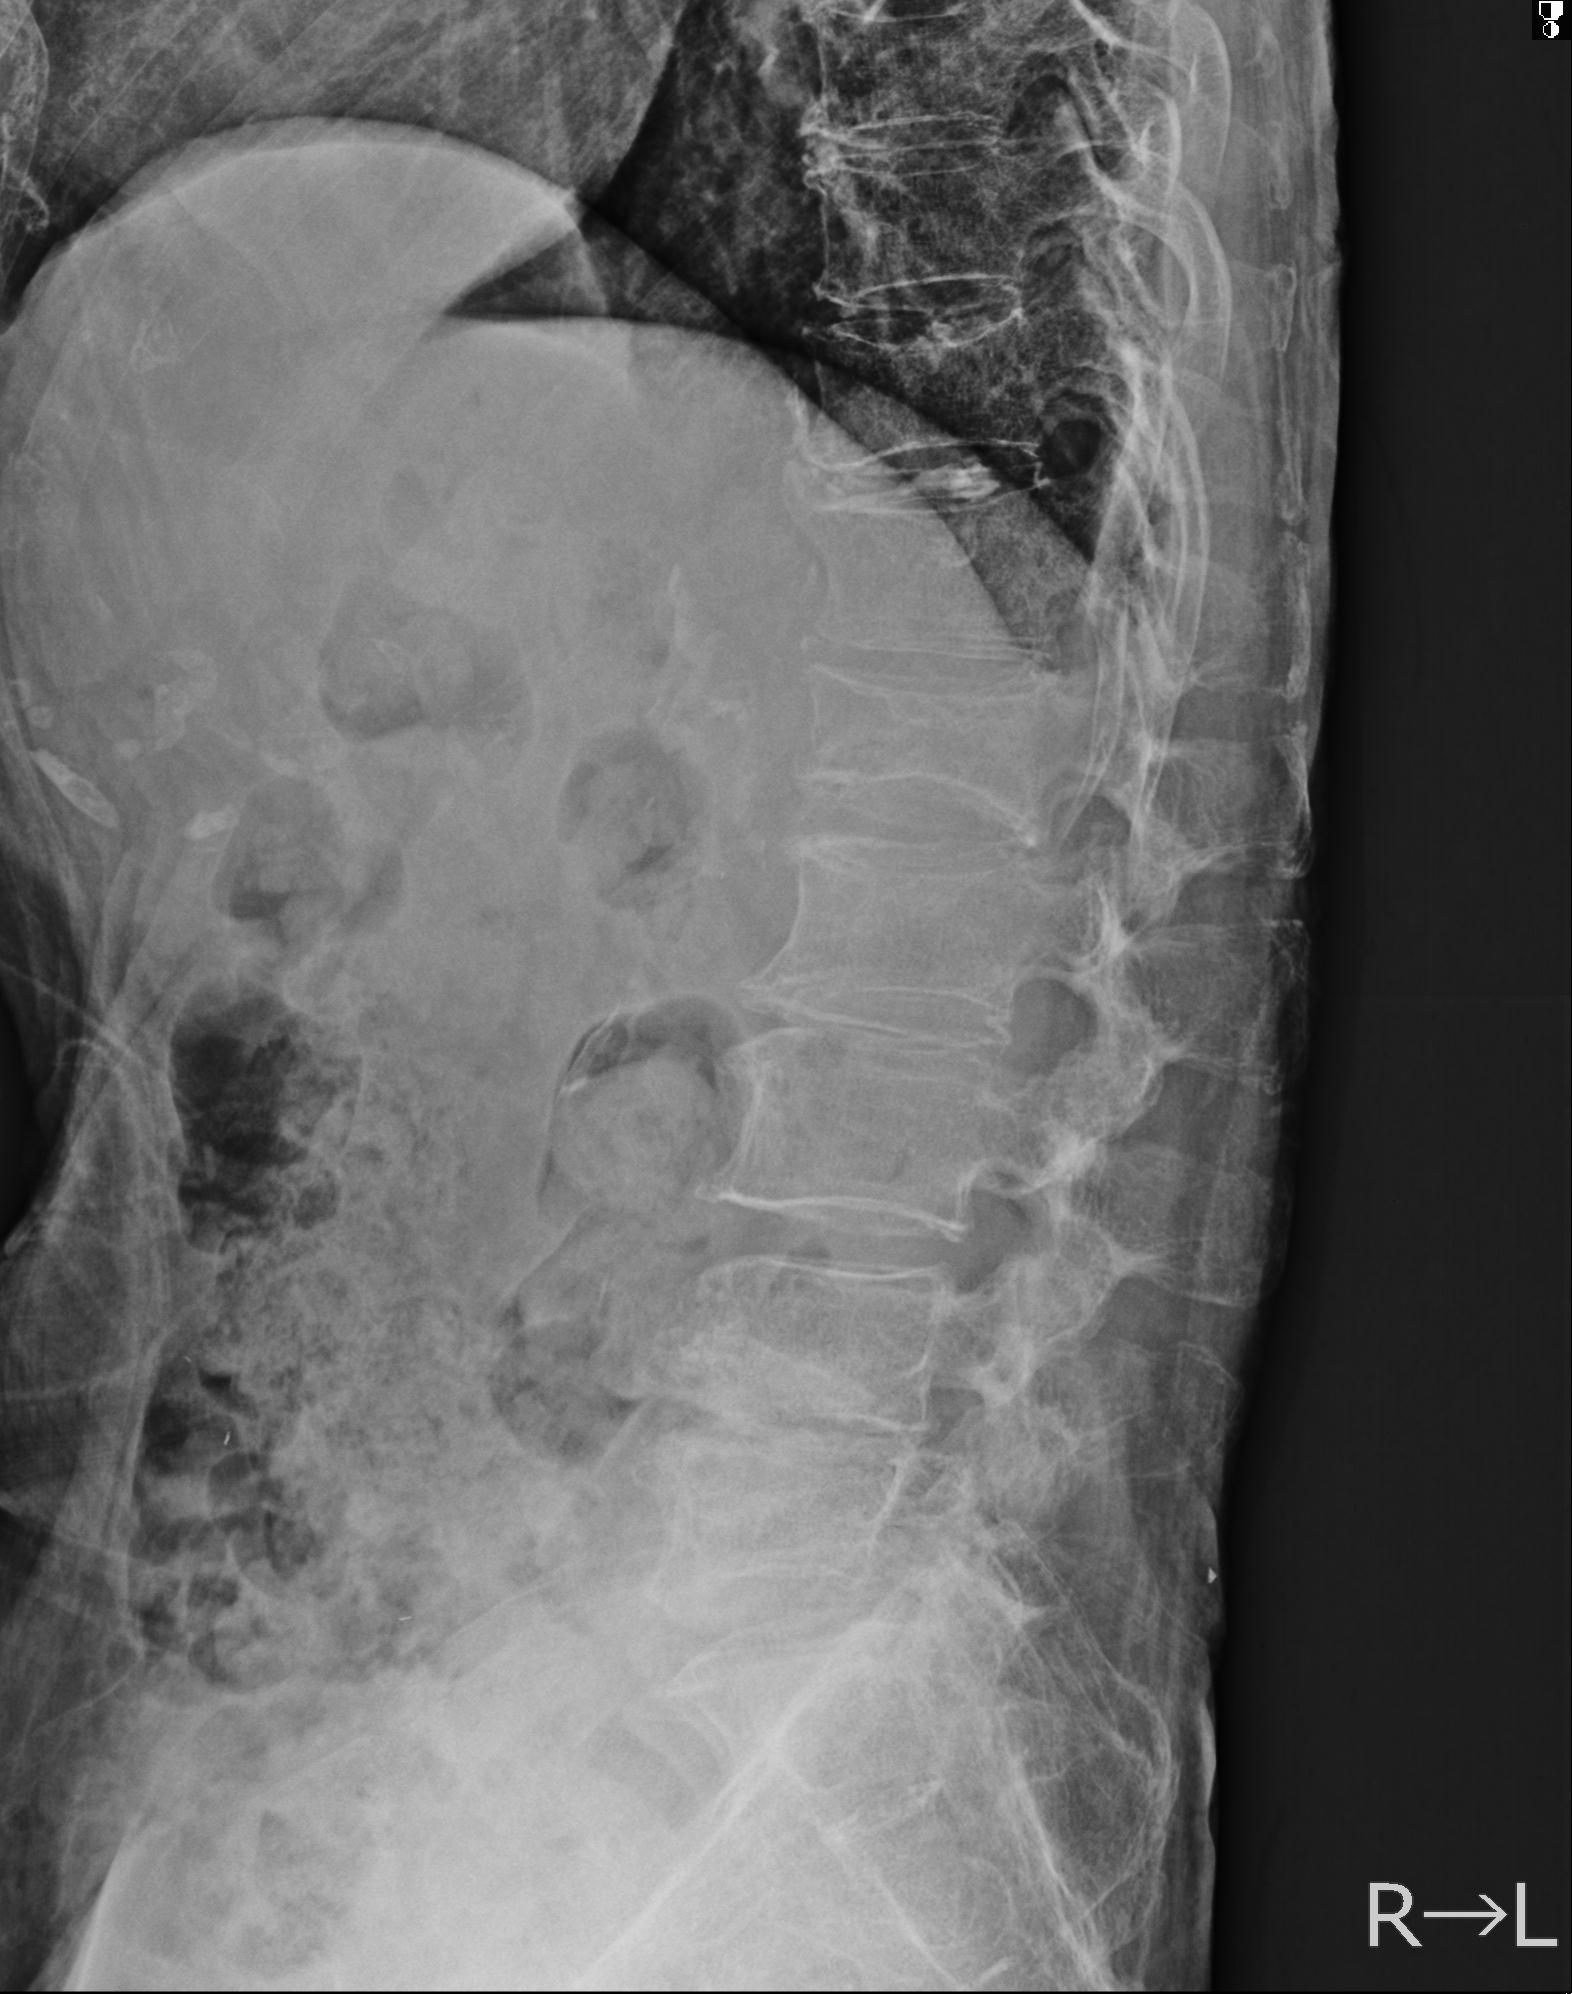

102916 2/1 と 3/22 腰椎 2R 74歳女性 LIFX